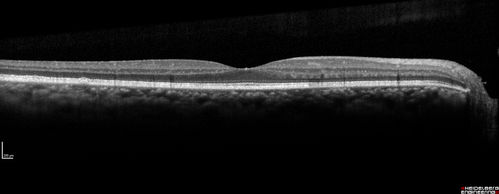

Ocular Lymphoma - non-Hodgkins - B-Cell - Right eye has equatorial drusen

Multifocal sub-RPE lesions in the left eye of a patient with history of Non-hodgkins B-cell Lymphoma last active 2 years ago